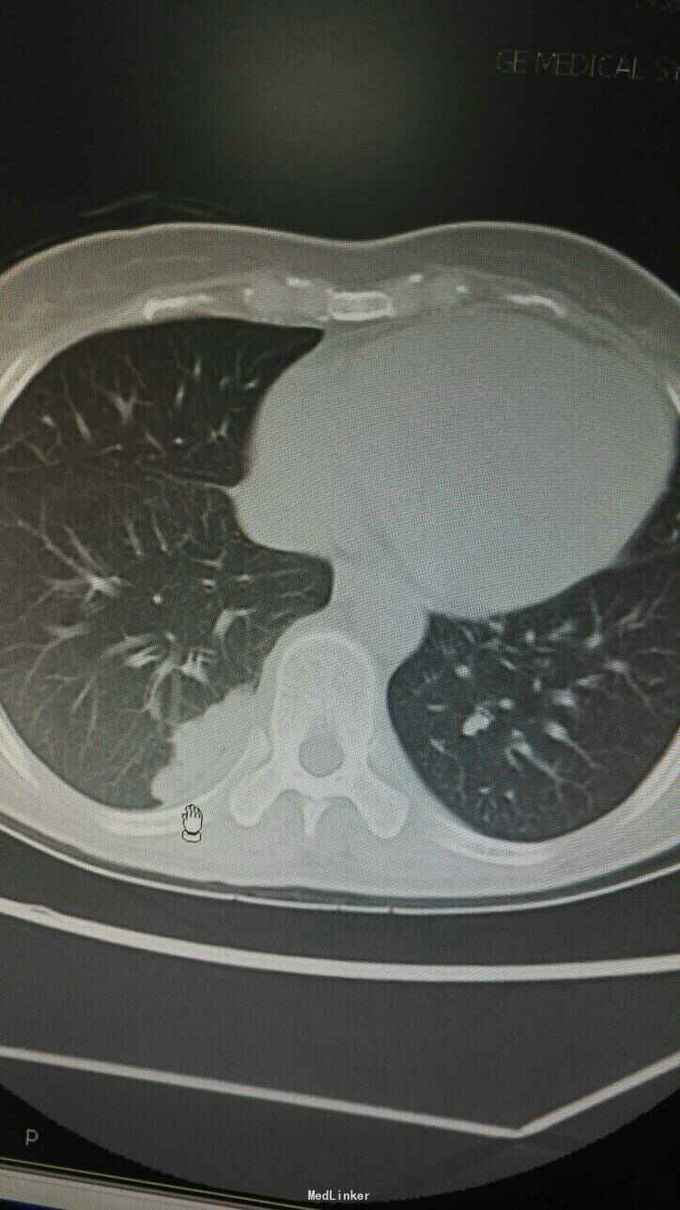

体温38.9℃,心率103。双肺呼吸音粗,未闻及干湿性罗音。心率快,律齐。腹无特殊。右下肢小腿肿胀,见外伤陈旧淤斑。胸部CT示双肺多发病灶,双上肺病灶考虑陈旧性结核,余病灶考虑感染?肿瘤?

入院诊断肺多发病灶查因:肺梗死伴感染?结核复发?肺癌?入院予抗感染,抗凝等治疗。查肿瘤指标,风湿指标未见异常,因甲亢未控制未行CT增强,行右肺病灶活检,未见肿瘤及肉芽肿,见较多坏死物。住院联合抗感染及抗凝,对症治疗后,患者发热胸痛症状好转。

患者体温正常,无明显胸痛。患者既往有下肢血栓病史,且肺病灶多在靠近胸膜处,胸痛明显,与血管分布一致,最后诊断考虑肺梗死伴感染。